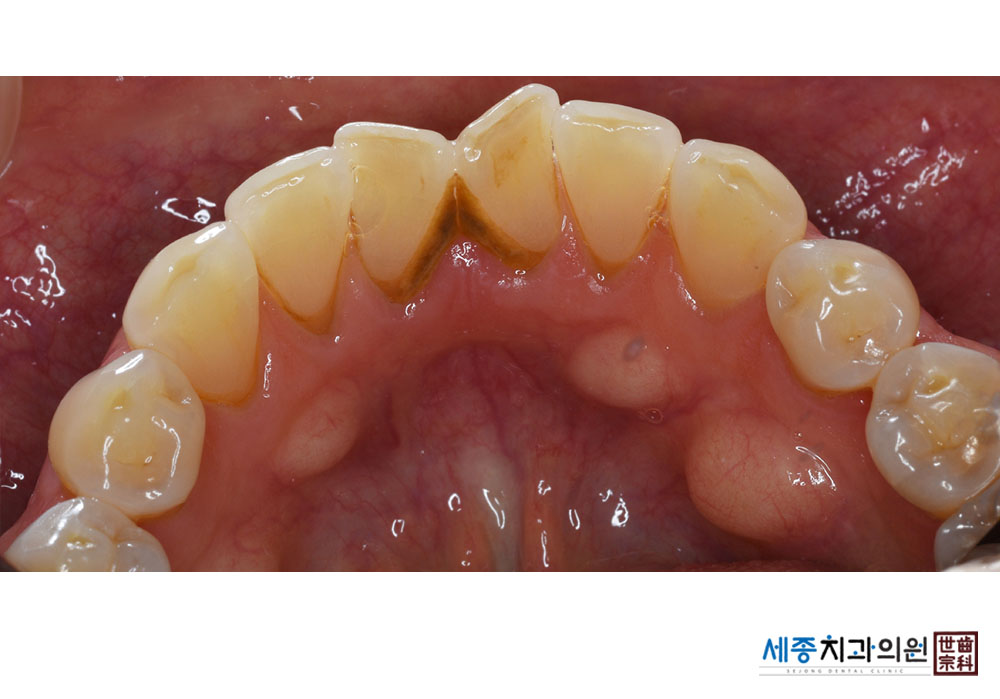

[스케일링] 치주질환 예방 스케일링

치료전 : 2021-01-29

가글마취&저주파 스켈러를 사용한 스케일링